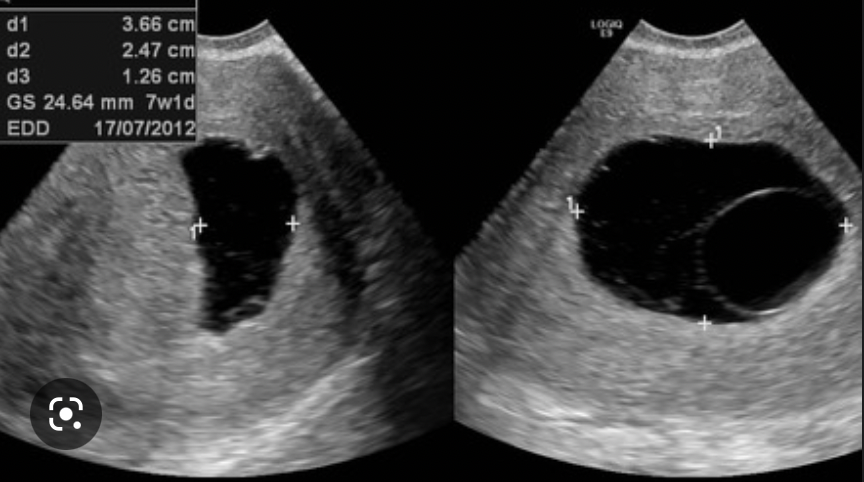

What 3 features are looked for on transvaginal US to determine the viability of a pregnancy?

A

• mean gestational sac diameter

• foetal pole + crown-rump length

• fetal heartbeat

mean gestational sac diameter

these appear sequentially so as each feature develops, the previous becomes less relevant in determining viability of a pregnancy

How is an anembryonic pregnancy diagnosed on transvaginal USS?

• a fetal pole is expected once mean gestational sac diameter is 25mm or more

• if the MGSD is >25mm and there is no fetal pole, scan is repeated after 1 week

• if the fetal pole is still not present, this is an anembryonic pregnancy